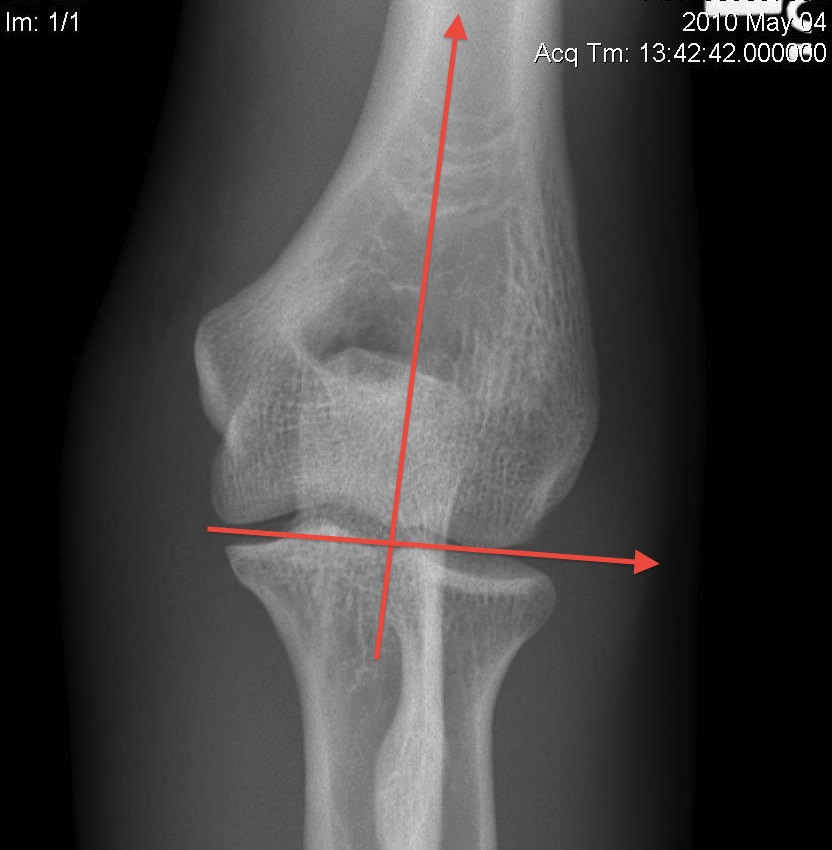

OTA / AO Classification

Type A: Extra-articular fracture

Type B: Partial articular fractures

Lateral condyle Medial condyle

Type C: Complete articular fractures